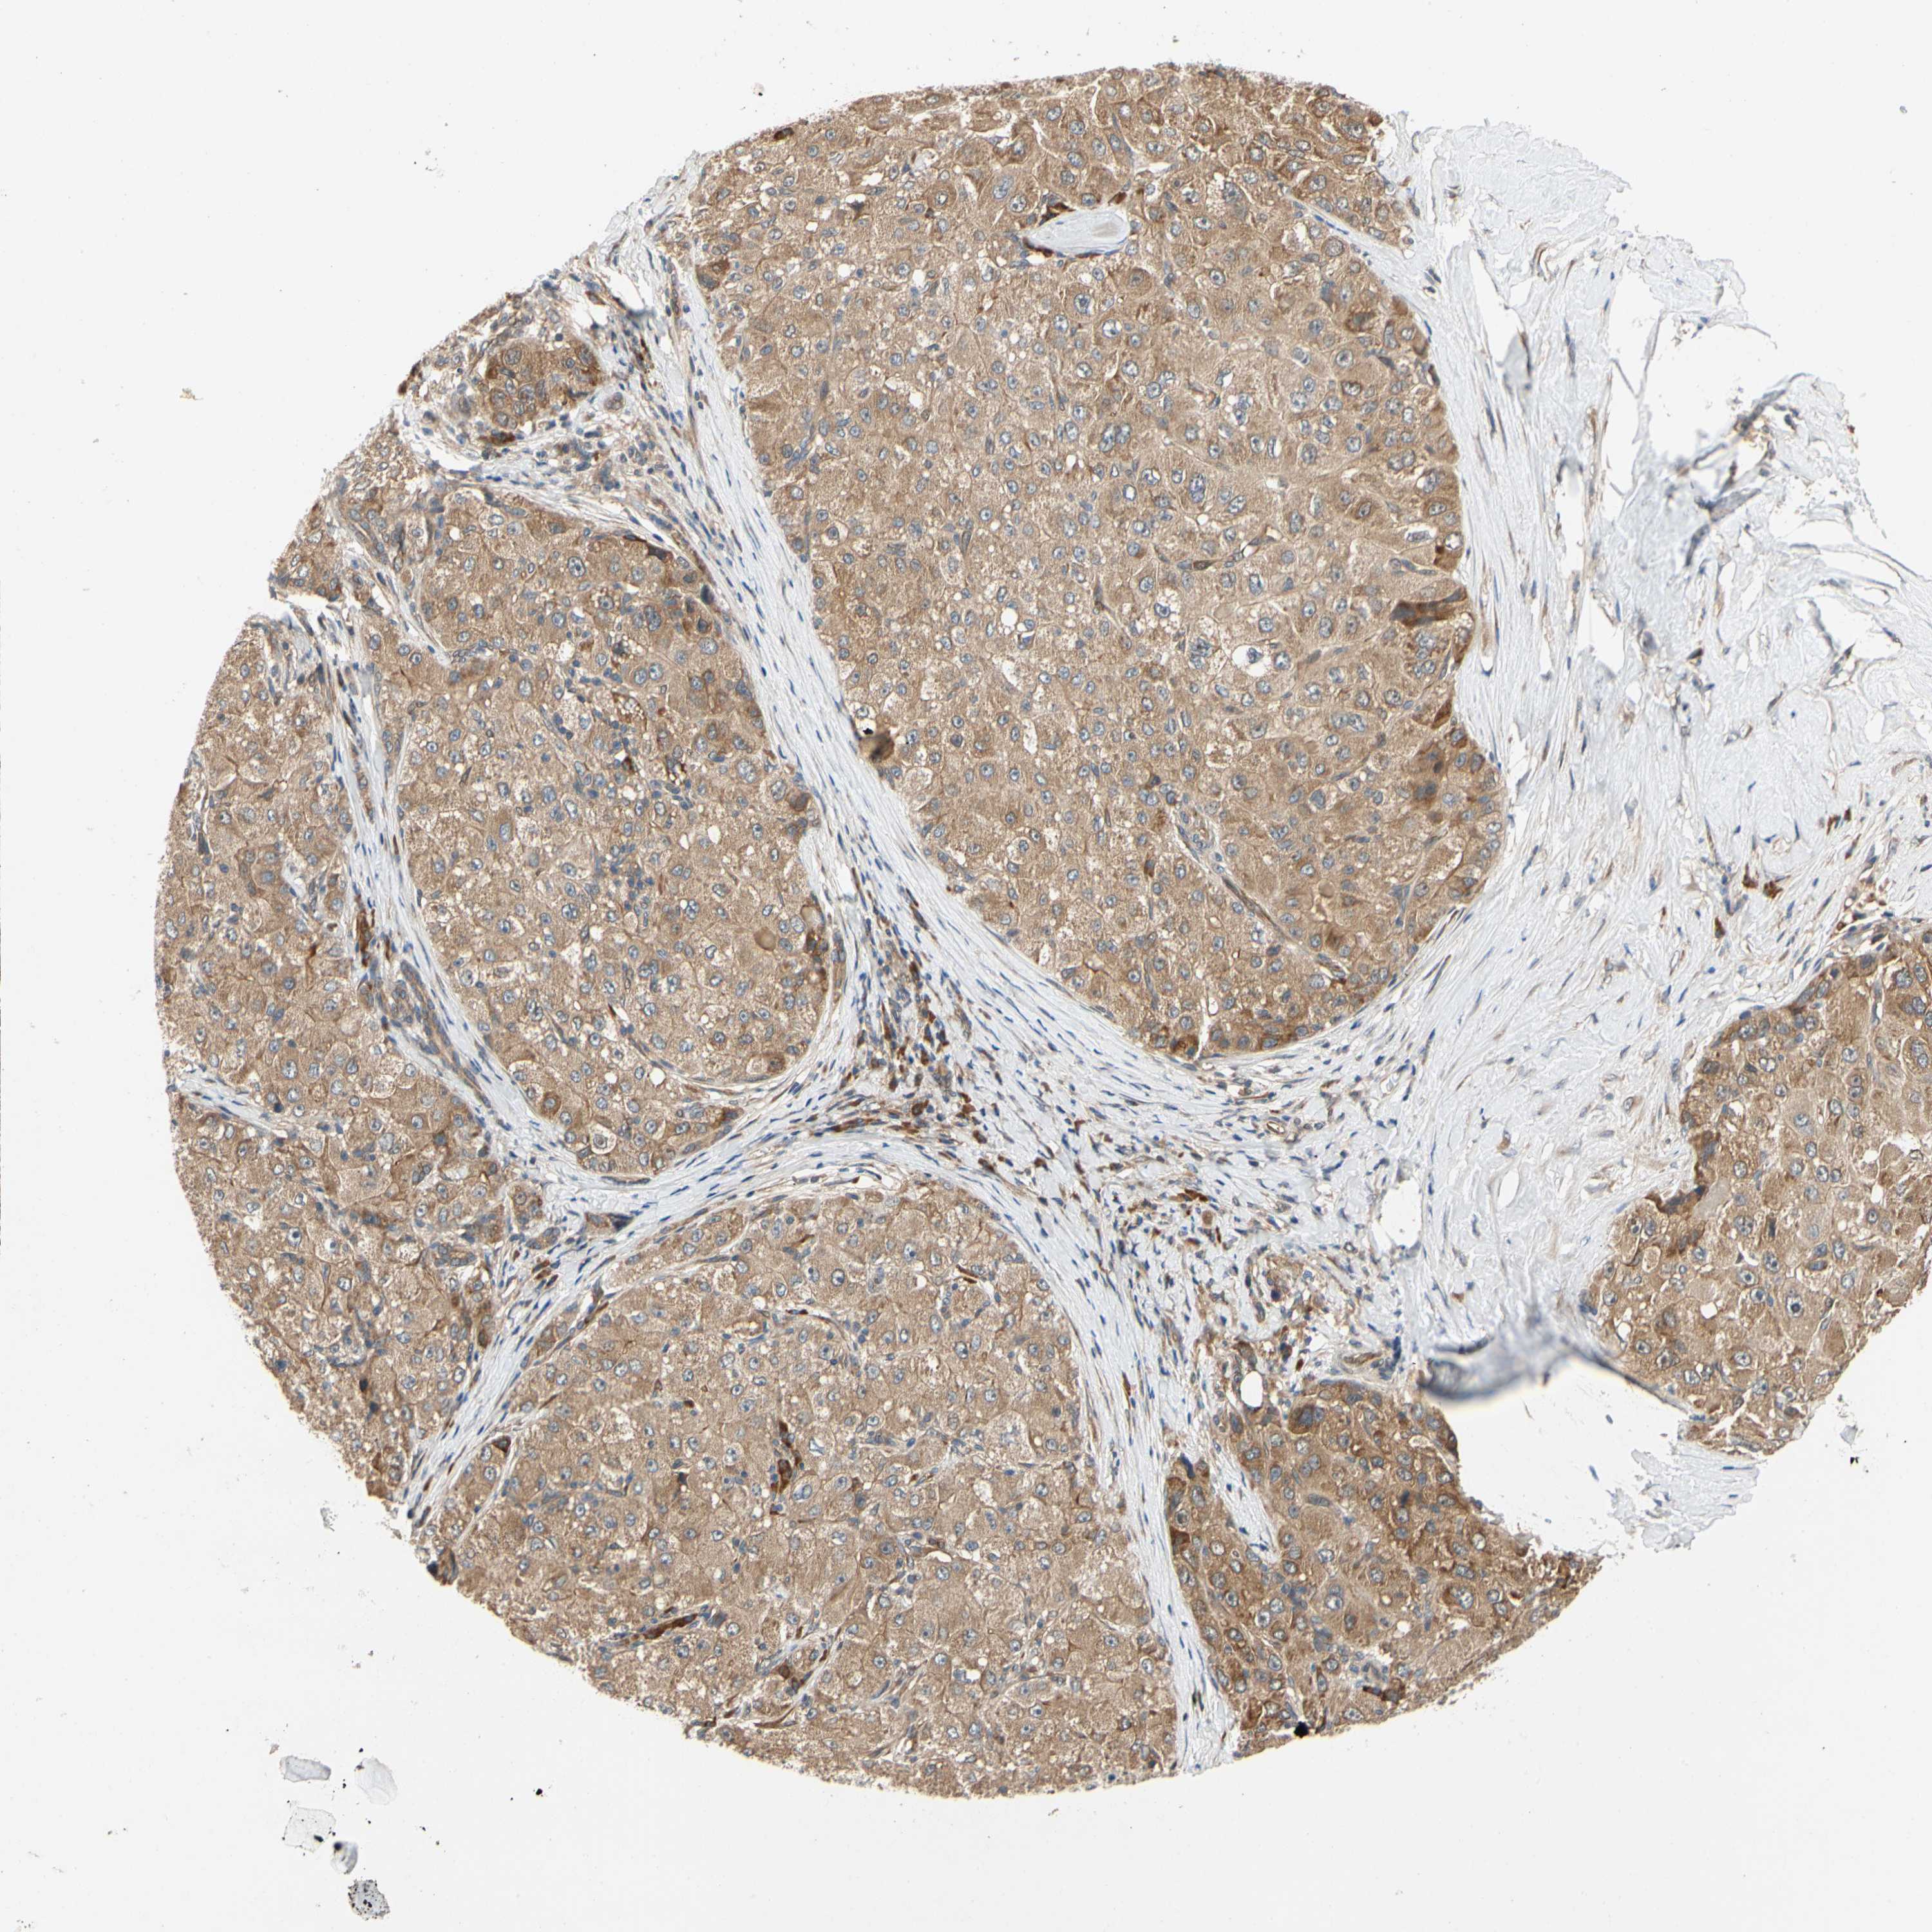

LIVER CANCER - Protein expressioni

A mouse-over function shows sample information and annotation data. Click on an image to view it in a full screen mode. Samples can be filtered based on level of antibody staining by selecting one or several of the following categories: high, medium, low and not detected. The assay and annotation is described here.

Note that samples used for immunohistochemistry by the Human Protein Atlas do not correspond to samples in the TCGA dataset.

Antibody stainingi

Antibody staining in the annotated cell types in the current human tissue is reported as not detected, low, medium, or high, based on conventional immunohistochemistry profiling in selected tissues. This score is based on the combination of the staining intensity and fraction of stained cells.

Each image is clickable and will lead to virtual microscopy that enables deeper exploration of all samples and also displays staining intensity scores, fraction scores and subcellular localization as well as patient and tissue information for each sample.

Antibody HPA008462

Staining

High

Medium

Low

Not detected

Intensity

Strong

Moderate

Weak

Negative

Quantity

>75%

75%-25%

<25%

None

Location

Nuclear

Cytoplasmic/membranous

Cytoplasmic/membranous,nuclear

Cholangiocarcinoma

Carcinoma, Hepatocellular, NOS